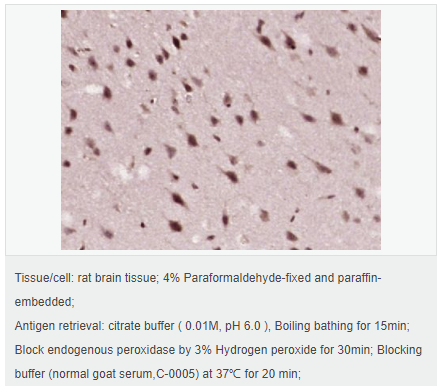

| 產(chǎn)品應(yīng)用 | WB=1:500-2000 ELISA=1:5000-10000 IHC-P=1:100-500 IHC-F=1:100-500 Flow-Cyt=1μg /test IF=1:100-500 (石蠟切片需做抗原修復(fù)) not yet tested in other applications. optimal dilutions/concentrations should be determined by the end user. |

| 細(xì)胞定位 | 細(xì)胞核 細(xì)胞漿 |

| 產(chǎn)品介紹 | ATF6 is a transcription factor that acts during endoplasmic reticulum stress by activating unfolded protein response target genes. It binds DNA on the 5'-CCAC[GA]-3'half of the ER stress response element (ERSE) (5'-CCAAT-N(9)-CCAC[GA]-3') and of ERSE II (5'-ATTGG-N-CCACG-3'). Binding to ERSE requires binding of NF-Y to ERSE. ATF6 could also be involved in activation of transcription by the serum response factor. ATF6 exists as a homodimer and heterodimer with ATF6 beta. The dimer interacts with the nuclear transcription factor Y (NF-Y) trimer through direct binding to NF-Y subunit C (NF-YC). It also interacts with the transcription factors GTF2I, YY1 and SRF. Under ER stress the cleaved N-terminal cytoplasmic domain translocates into the nucleus. The basic domain of ATF6 functions as a nuclear localization signal and the basic leucine zipper domain is sufficient for association with the NF-Y trimer and binding to ERSE. During the unfolded protein response an approximately 50 kDa fragment containing the cytoplasmic transcription factor domain is released by proteolysis. The cleavage seems to be performed sequentially by site 1 and site 2 proteases. ATF6 is N glycosylated, phosphorylated in vitro by MAPK14/P38MAPK and belongs to the bZIP family. Function: Transcription factor that acts during endoplasmic reticulum stress by activating unfolded protein response target genes. Binds DNA on the 5'-CCAC[GA]-3'half of the ER stress response element (ERSE) (5'-CCAAT-N(9)-CCAC[GA]-3') and of ERSE II (5'-ATTGG-N-CCACG-3'). Binding to ERSE requires binding of NF-Y to ERSE. Could also be involved in activation of transcription by the serum response factor. Subunit: Homodimer and heterodimer with ATF6-beta. The dimer interacts with the nuclear transcription factor Y (NF-Y) trimer through direct binding to NF-Y subunit C (NF-YC). Interacts also with the transcription factors GTF2I, YY1 and SRF. Subcellular Location: Endoplasmic reticulum membrane; Single-pass type II membrane protein. Processed cyclic AMP-dependent transcription factor ATF-6 alpha: Nucleus. Note=Under ER stress the cleaved N-terminal cytoplasmic domain translocates into the nucleus. Tissue Specificity: Ubiquitous. Post-translational modifications: During unfolded protein response an approximative 50 kDa fragment containing the cytoplasmic transcription factor domain is released by proteolysis. The cleavage seems to be performed sequentially by site-1 and site-2 proteases. N-glycosylated. The glycosylation status may serve as a sensor for ER homeostasis, resulting in ATF6 activation to trigger the unfolded protein response (UPR). Phosphorylated in vitro by MAPK14/P38MAPK. Similarity: Belongs to the bZIP family. ATF subfamily. Contains 1 bZIP (basic-leucine zipper) domain. SWISS: P18850 Gene ID: 22926 Database links: Entrez Gene: 22926 Human Entrez Gene: 226641 Mouse Omim: 605537 Human SwissProt: P18850 Human Unigene: 492740 Human Important Note: This product as supplied is intended for research use only, not for use in human, therapeutic or diagnostic applications. |